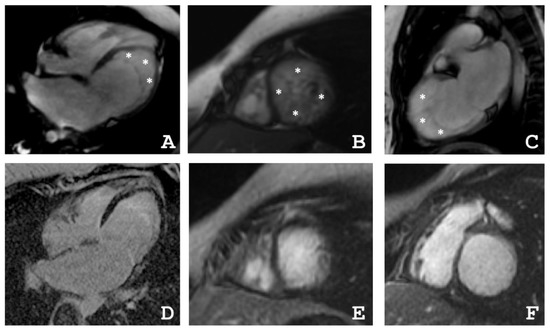

4.2. Cardiac Magnetic Resonance Imaging

| Patient | The Ratio NC/C in Segments | ||||||||||||||||

|---|---|---|---|---|---|---|---|---|---|---|---|---|---|---|---|---|---|

| 1 | 2 | 3 | 4 | 5 | 6 | 7 | 8 | 9 | 10 | 11 | 12 | 13 | 14 | 15 | 16 | 17 | |

| III-2 | 0 | 0 | 0 | 0 | 0 | 1.1 | 4.0 | 0 | 0 | 1.6 | 2.1 | 3.5 | 0 | 0 | 1.4 | 0 | 0 |

| III-4 | 1.2 | 0 | 0 | 0 | 1.2 | 2.2 | 1.1 | 0 | 0 | 3.8 | 3.0 | 3.0 | 4.9 | 3.3 | 3.5 | 2.8 | 5.9 |

| IV-3 | 3.3 | 1 | 0 | 0 | 0 | 0 | 3.5 | 2.5 | 1.1 | 0 | 0 | 1 | 8.3 | 8.3 | 6.3 | 8.3 | 10.5 |

| Patient | EDV | EF | Grothoff, [16] | Jacquier, % [17] | Petersen, [18] | |||

|---|---|---|---|---|---|---|---|---|

| Mass Index of NC, g/m² | NC/Myocardial mass, % | NC/C ≥ 3:1 in One Segment(1–3, 7–16) | NC/C ≥ 2:1 in 4–6th Segments | |||||

| III-2 | 77 | 31 | 12 | 20 | + | − | 20 | + |

| III-4 | 82 | 55 | 8 | 14 | + | + | 16 | + |

| IV-3 | 64 | 48 | 21 | 36 | + | − | 36 | + |